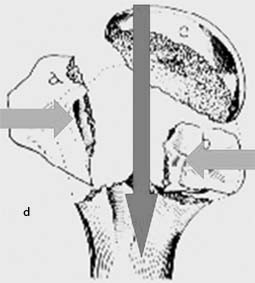

Die Operation beinhaltet 2 wesentliche Schritte. Zum einen wird durch Implantation des Nagels, Fixieren der Kalotte an den Nagel mit der proximalsten Verriegelungsschraube und Fixieren des Nagels im Schaft durch Besetzen beider Schaftschrauben die Stellung der Kalotte zum Schaft fixiert. Zum anderen müssen eine subtile Rekonstruktion und Retention der Rotatorenmanschette, d. h. der Tuberkel, erfolgen, zum einen mit den zur Verfügung stehenden Verriegelungsschrauben, zum anderen durch großzügige Verwendung zusätzlicher Sicherungsnähte, um die Rotatorenmanschette an den Schrauben zu fixieren (Abb. 8).

Operationsschritte: dunkler Pfeil Fixierung der Kalotte am Schaft durch den Nagel, helle Pfeile Reposition der Tuberkel und anschließende Retention durch Verriegelungsschrauben mit Zuggurtungen